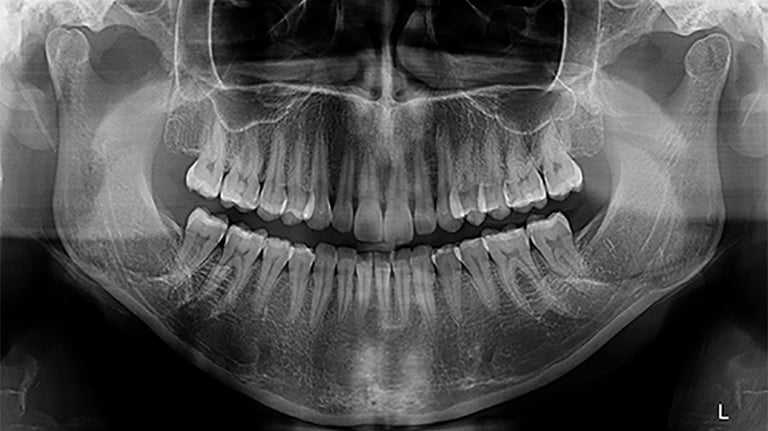

RADIOGRAFIA PANORÂMICA